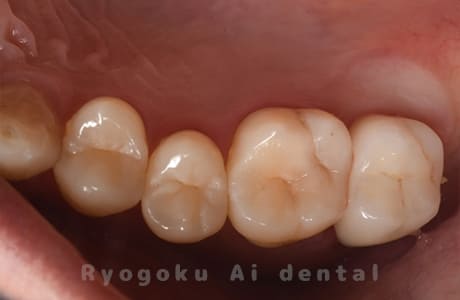

Case37

-

- 原因

- 補綴物二次カリエス

- 治療内容

- 24番ダイレクトボンディング、25番セラミックインレー修復、26・27番セラミッククラウン修復

- 治療費用

- 387,000円

歯がしみるとのことでご来院された患者様です。銀歯の中が大きく虫歯になっておりました。セラミックの材料で再治療を行いました。

<リスク・副作用>

過度の咬合や衝撃で割れることがあります。術後は痛み、腫れ、痺れなどの副作用が生じる場合があります。